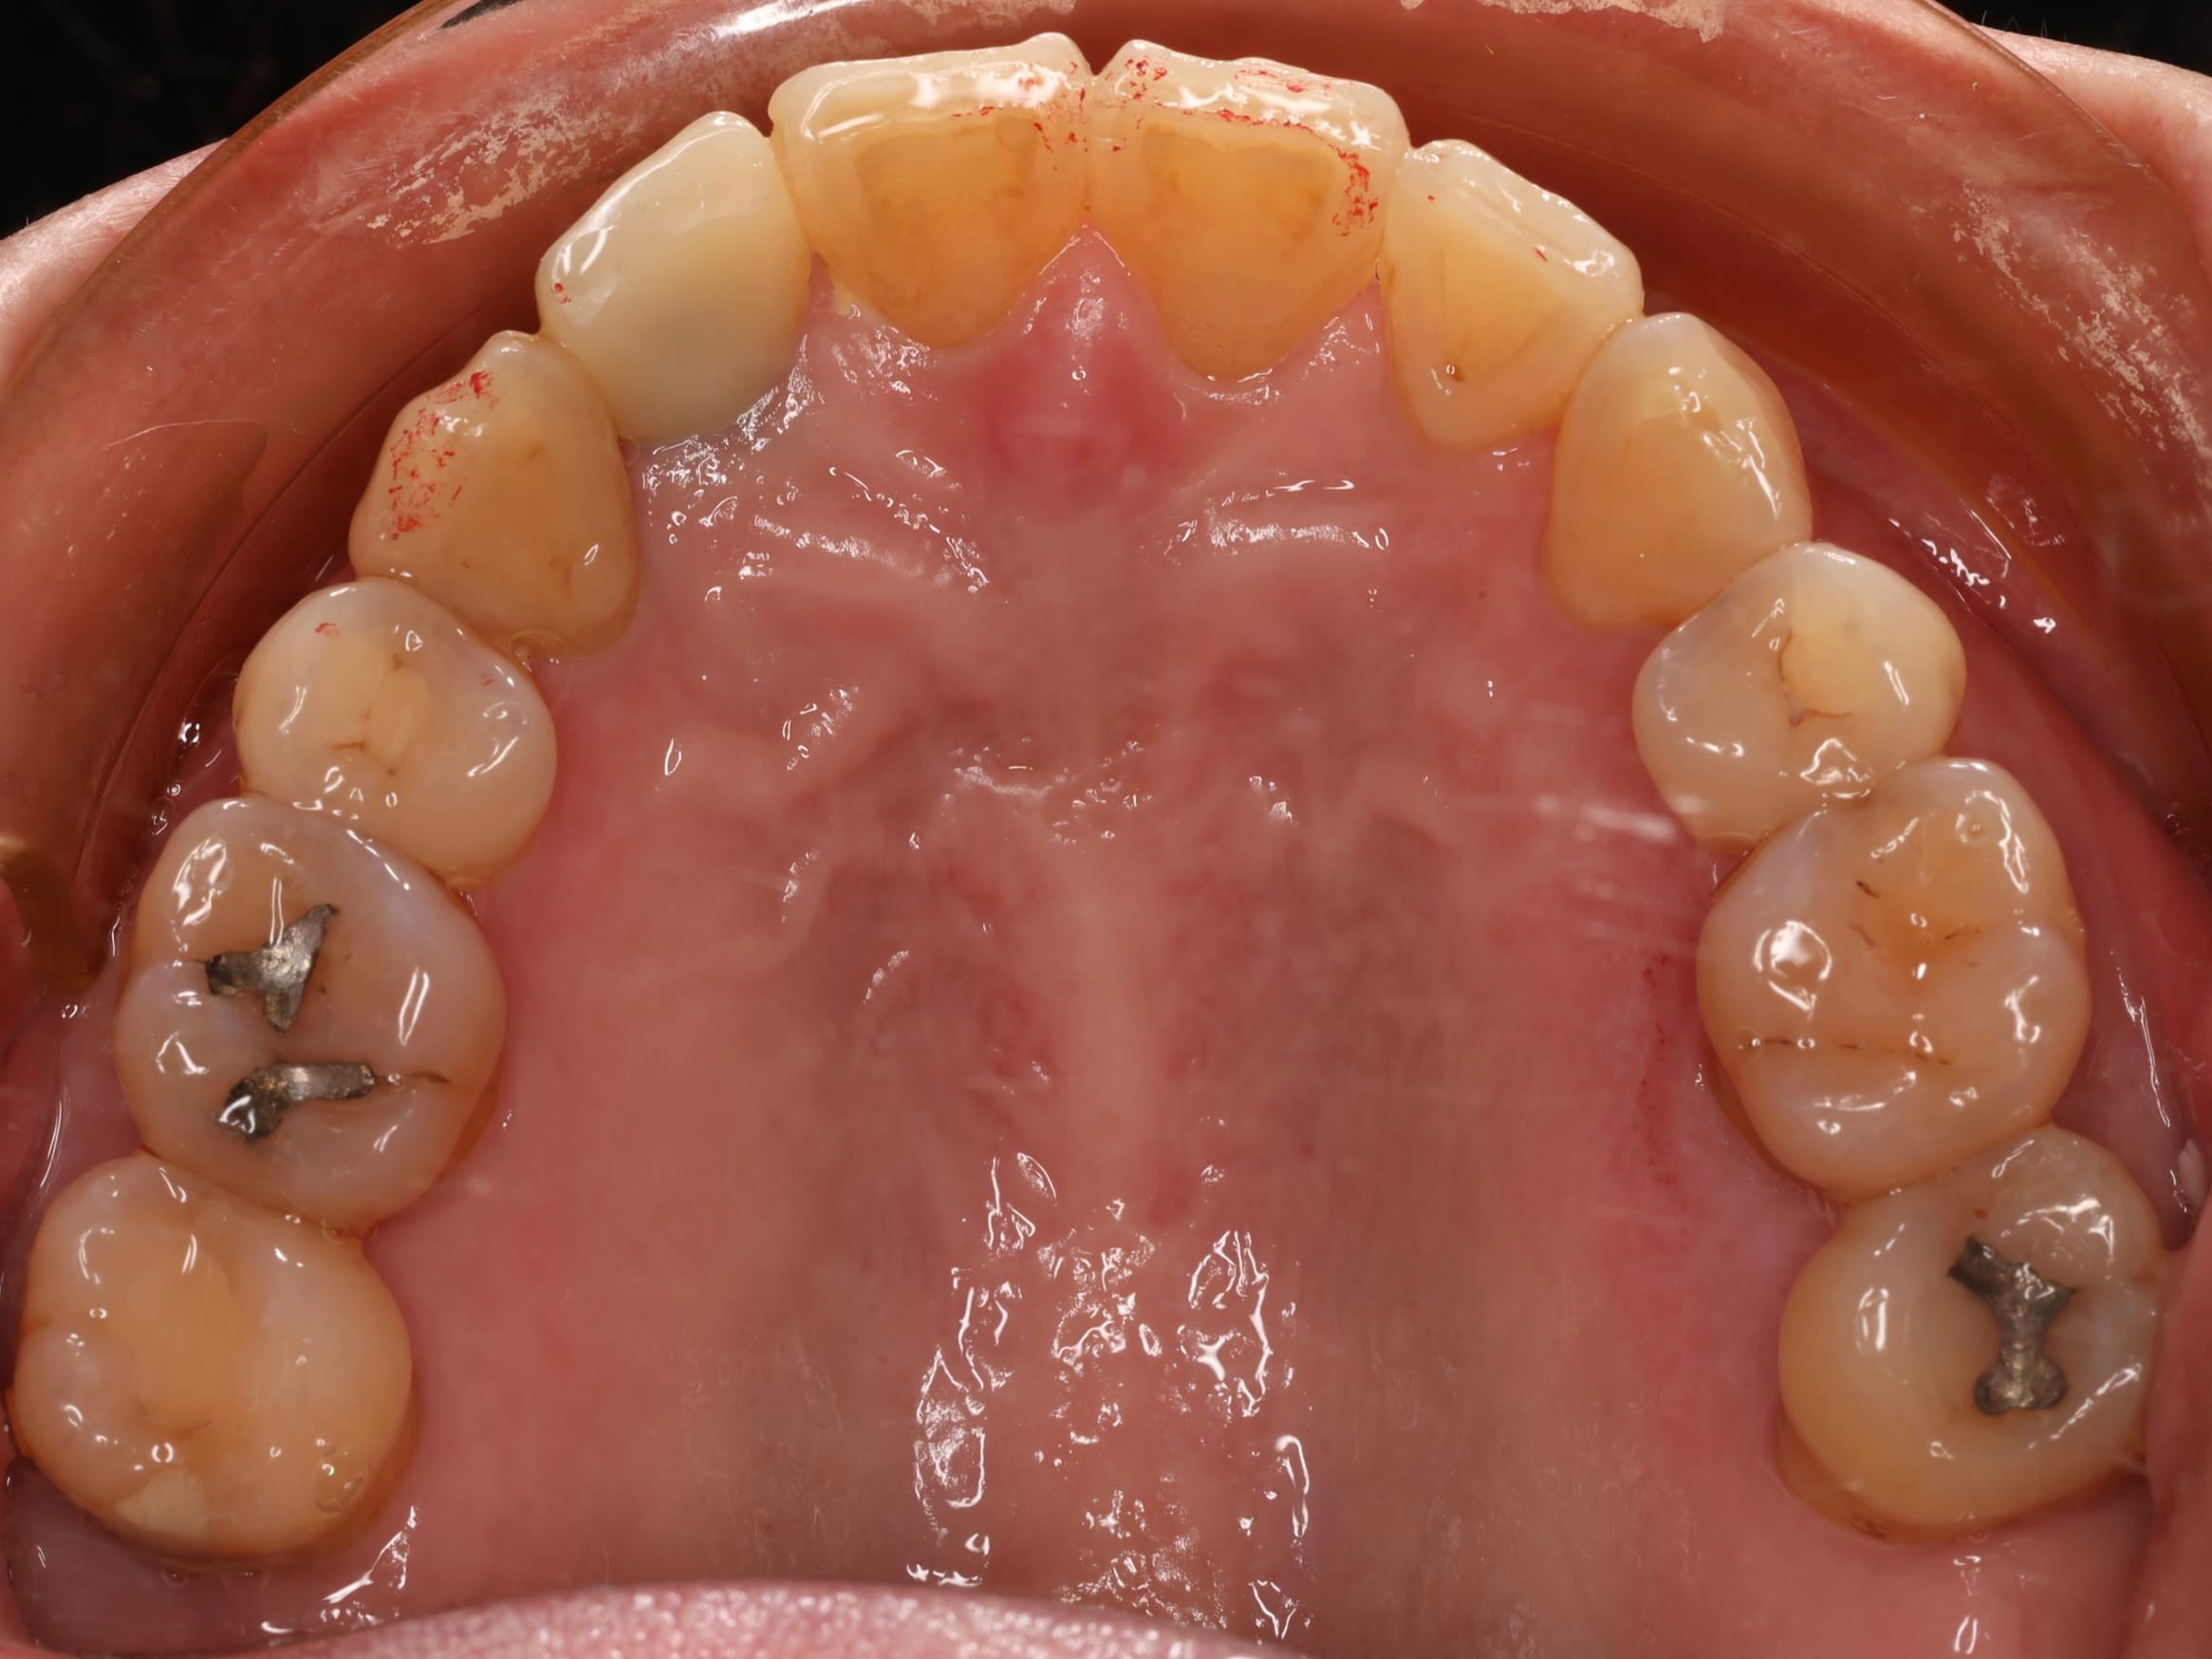

首先是 牙齒排列不整,她年輕時曾接受過矯正治療,但因為沒有持續佩戴維持器,導致牙齒在不知不覺間位移,不僅影響外觀,也讓日常清潔變得困難。再來是 牙周病問題,雖然患者有在其他診所進行治療,但由於右下側有一顆牙齒搖晃得非常厲害,牙周破壞的情況相當嚴重,原本的醫師告知她可能無法保留。最後是 舊假牙美觀不佳 的問題,患者的右上側門牙曾做過植牙治療,但牙套的角度讓牙齒看起來有些傾斜,並非正對前方,視覺上顯得不協調。此外,口內還有一些早期製作的舊牙套,邊緣都露出黑黑的金屬邊,每次張嘴說話都感到不自在。

牙周問題是進行任何治療之前必須優先解決的課題,有健康的牙周組織,才能為後續的治療奠定穩固基礎,因此第一步先將牙齦和齒槽骨的發炎狀況控制好,為之後的矯正治療及假牙重建做好準備。

由於患者一直對舊假牙的金屬黑邊感到困擾,因此在牙周狀況穩定後,我們接著處理下排小臼齒區域的問題,將舊牙套逐一拆除,仔細檢查牙齒內部的狀況,需要重新根管治療的牙齒先予以處理,接著裝上臨時假牙,這樣一來,患者在接下來的矯正治療期間,牙齒也能維持一定的美觀。

由於患者的牙齒天生形狀偏三角形,又因為牙周病造成牙齦萎縮。之前因為下排牙齒擁擠,這個問題並不明顯,但當矯正完成、牙齒排列恢復正常後,牙縫間的空隙反而特別顯眼。因此在整個治療的最後一步,我們利用全瓷貼片改變牙齒的形狀,讓牙齒變得更方正,並有效改善黑三角問題,達到整體外觀的和諧一致。